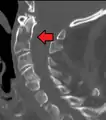

A fracture of the base of the dens as seen on plain X-ray

A fracture of the base of the dens as seen on CT

Type 3 odontoid fracture

Type 2 dens fracture